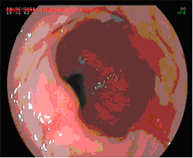

El diagnóstico se lleva a cabo mediante endoscopios de alta resolución con magnificación (aumento de la imagen), utilizando técnicas de cromoendoscopia añadidas, realizadas por endoscopistas especialistas en el diagnóstico precoz de lesiones precancerosas y la realización de biopsias que son analizadas.

Mucosectomía endoscópica

La mucosectomía consiste en la resección por vía endoscópica de una sección de la mucosa y submucosa (en este caso esofágica). Esta indicada siempre que en la endoscopia diagnóstica se aprecien lesiones sobreelevadas en el esófago de Barrett.